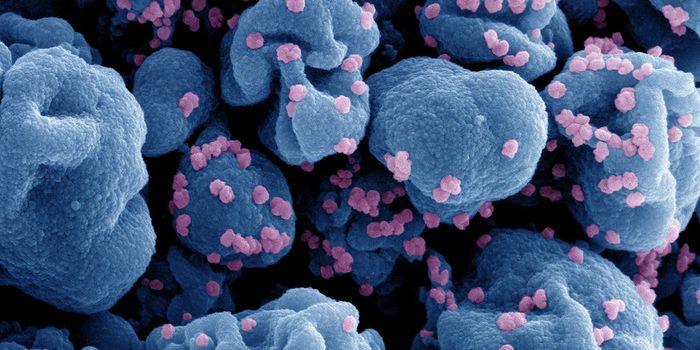

JUL 19, 2016CancerA decade-old technology to arm the immune system to fight cancer is now being adapted to fight HIV, one of the most pern ...